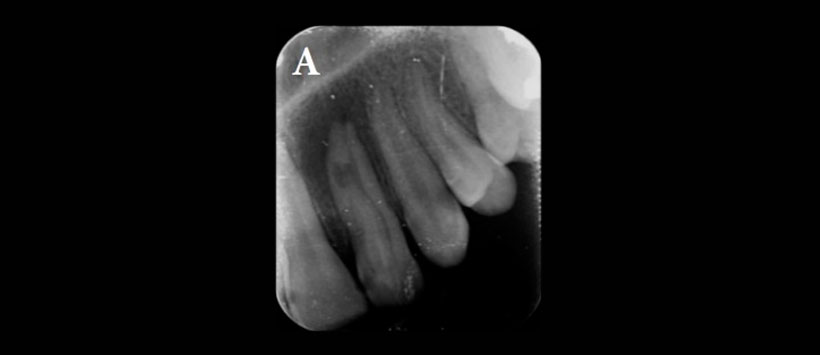

El presente caso es de una paciente de sexo femenino de 12 años de edad que fue derivada al departamento de manifestando dolor en el incisivo lateral superior izquierdo El examen extraoral inicial no reveló hinchazón en el lado izquierdo del maxilar. Había una fosa palatina en el diente 2.2 (Figura 1) y el diente era sensible a la palpación y la percusión. Una radiografía periapical inicial y CBCT mostraron la presencia de DI tipo 2 (Oehler) en el diente, asociado a radiolucides periapical y reabsorción de raíz interna (Figura 2). Dado que la morfología de la invaginación no era clara en la radiografía periapical, se usó CBCT para un diagnóstico y protocolo de tratamiento óptimos. El escaneo CBCT reveló dos canales separados. El canal invaginado estaba casi en el centro de la raíz, pero el otro canal estaba localizado mesiolingualmente. También se observó la reabsorción de la raíz asociada con el canal invaginado (Figura 3). El paciente fue tratado en dos sesiones. En la primera visita, se aplicó anestesia local con lidocaína al 2% que contenía epinefrina y se aisló el diente con dique de goma. La cavidad de acceso endodóntico fue preparada. Luego, la longitud de trabajo se determinó mediante radiografía periapical y el localizador de ápices. El canal invaginado se encontró fácilmente y el segundo canal se encontró usando CBCT.